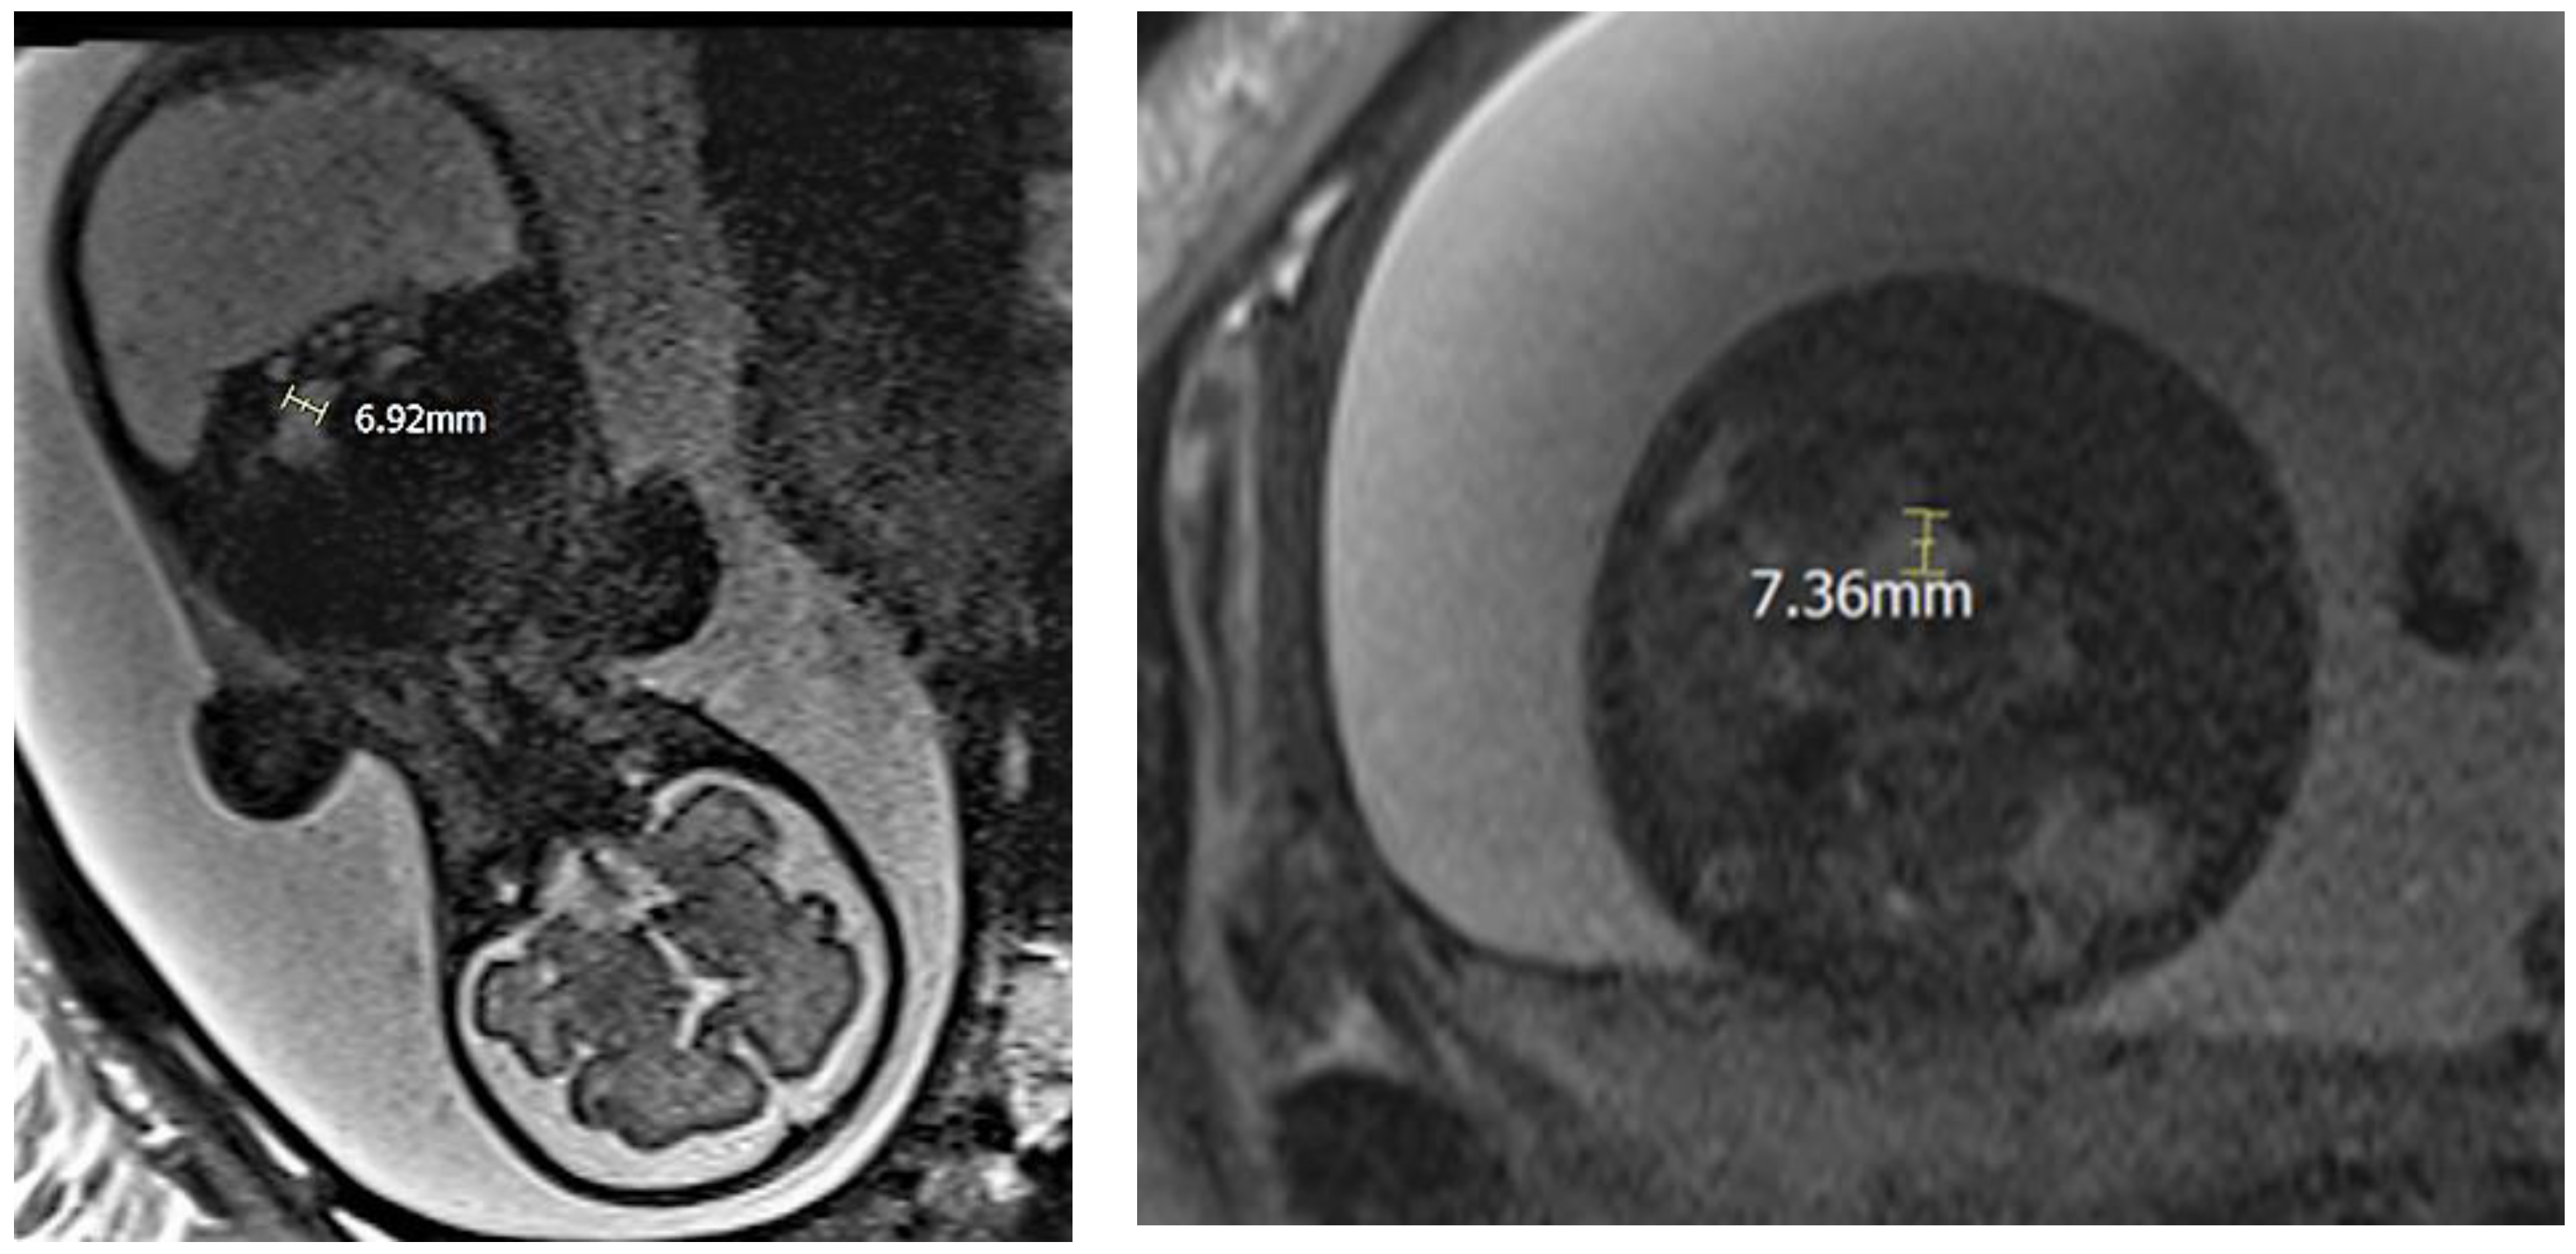

2.1. Case 1

2.2. Case 2